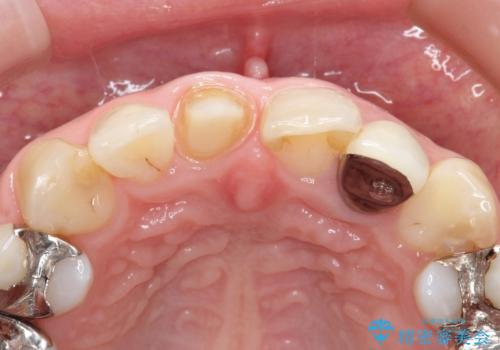

- 他院で装着された保険の前歯のかぶせ物が、他と歯と馴染まないので、自然な歯にしたいとのことで来院されました。

右上の1番目の歯の保険のかぶせ物と金属の土台を、ファイバーコアとオールセラミックにて再補綴する計画としました。

形態も色調もまわりの歯とは、調和がとれておらず、目立っていました。